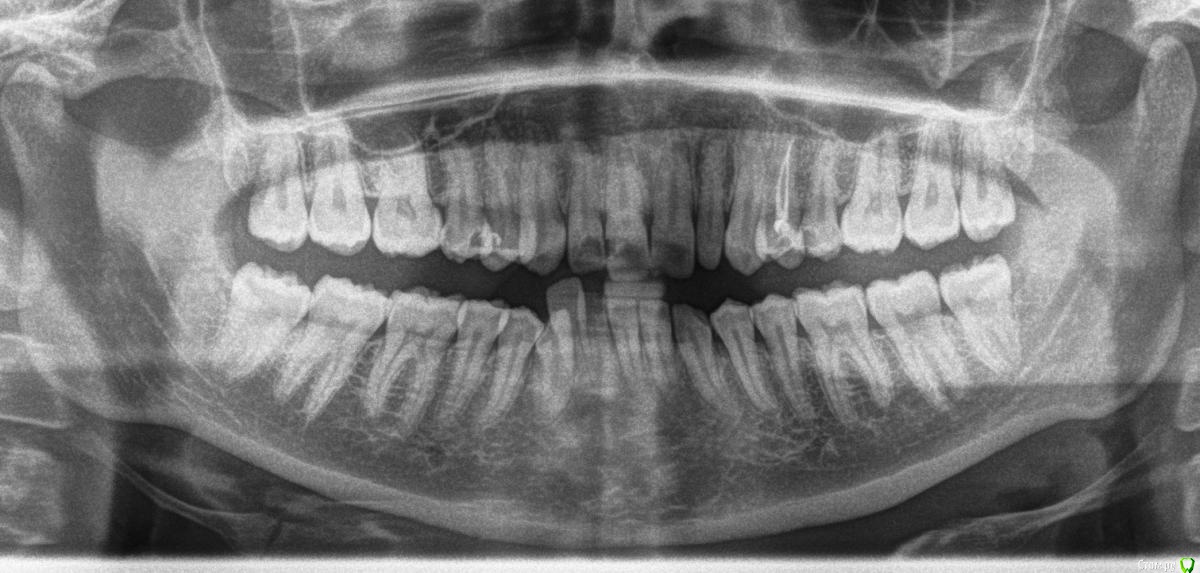

Евлампий Опубликовано 23 апреля, 2015 Поделиться Опубликовано 23 апреля, 2015 Всем доброго дня.Исправлять прикус или оставить все как есть? Пол женский, возраст 30лет, прикус неправильный с детства. Явных функциональных проблем нет: в боковых отделах зубы смыкаются нормально, повышенной стираемости, клиновидных дефектов нет, пародонт в порядке. ВНЧС тоже внешне никак себя не проявляет, щелчков нет, рот открывается нормально Но сделав ОПТГ по другому поводу обнаружилась сильная ассиметрия ветвей нижней челюсти и суставных головок. Исправлять ли прикус в целях предупреждения возможных проблем с ВНЧС в будущем или лучше оставить все как есть? Эстетика решающего значения не имеет. Благодарю вас. Ссылка на комментарий

Евлампий Опубликовано 30 апреля, 2015 Автор Поделиться Опубликовано 30 апреля, 2015 Докладываю)Побывала на консультации у нескольких докторов. В общем, сколько врачей столько мнений.Кто-то пугал, что по-любому рано или поздно зубы загнуться из-за неправильного прикуса и немедленно надо все исправлять.Кто-то говорил, что по суставу не критично, но скученность на нижней челюсти желательно поправить. (т.е. больше в эстетических целях, я так поняла это все надо делать)А один доктор сказал что только по одной ОПТГ судить о состоянии сустава нельзя, но предрасположенность есть - ассиметрия правой и левой половины и слабовыраженные суставные бугорки. (этот док мне понравился больше всего, но он не ортодонт ) Навскидку, пока без дополнительных обследований предполагают лечение с удалением премоляров на верхней челюсти. На мой вопрос, как это отразится на суставе, дают очень расплывчатые ответы. Жду ваших ответов.1.Целесообразно ли исправлять прикус в моей ситуации?2.Возможно ли обойтись без удаления на верхней челюсти и целесообразно ли это? 3. Самый главный вопрос - в моем случае брекетами по большей части можно улучшить только эстетику или и эстетику и функцию тоже (под функцией понимается в первую очередь сустав)? Как удаление отразится на ВНЧС? Спасибо. Ссылка на комментарий

Scrabble Опубликовано 14 мая, 2015 Поделиться Опубликовано 14 мая, 2015 Я не ортодонт, сразу предупреждаю. Но совершенно очевидно, что ортодонтия Вам необходима. И, скорее всего, в сочетании с ортогнатической хирургией. Без ТРГ вряд ли что-то определённое можно сказать. А что касается пломб на премолярах-Вам нужны керамические вкладки(они будут точно вопроизводить архитектонику окклюзионной поверхности зубов-с учётом функции) 2 Ссылка на комментарий